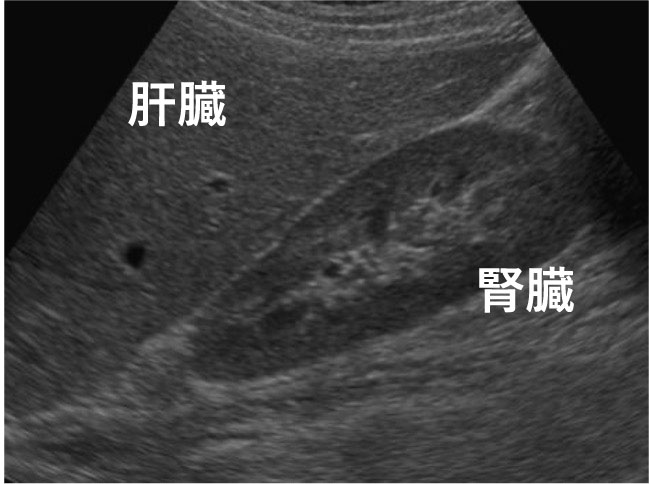

下図のように、肝臓と腎臓の濃淡の差(肝腎コントラスト)を脂肪肝の程度の参考基準にします。

正常な肝臓

正常な肝臓は腎臓とほぼ同じ濃淡を⽰します

脂肪肝

脂肪が溜まった肝臓は腎臓と⽐較して⽩く表⽰されます